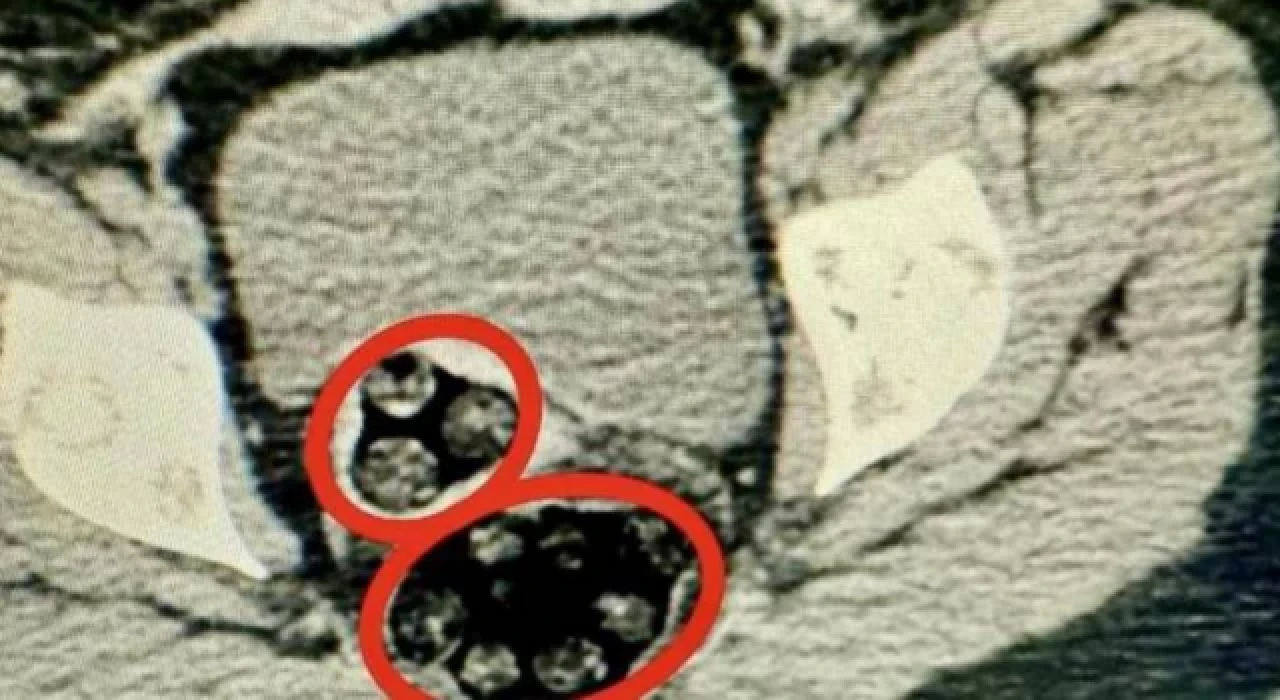

Kars'ta, polisin durdurduğu yolcu otobüsünde hareketinden şüphelenilen İran uyruklu yolcunun hastanede çekilen röntgeninde, makatında uyuşturucu tespit edildi. Uyuşturucu doğal yolla çıkarılırken, şüpheli tutuklandı.

Kars Harakani Devlet Hastanesi'ne götürülen Yenkejeh'in çekilen röntgeninde, makatında uyuşturucu tespit edildi. Doğal yolla kadının makatından 94 parça halinde toplam 550,93 gram metamfetamin çıkarıldı.